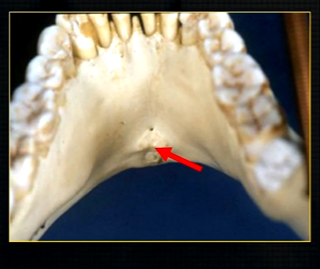

anterior lingual/inner aspect of the mandible

bony spurs

genial tubercules - muscles of the tongue and neck attach here

lingual pit

lower occlusal

small bony spurs of the genial tubercles